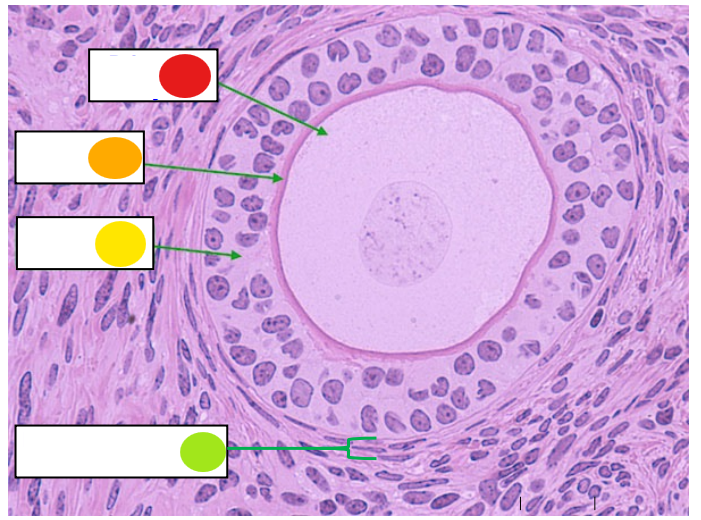

red

granulosa cells

orange

thecal cells

yellow

zona pellucida

What is this

secondary follicle